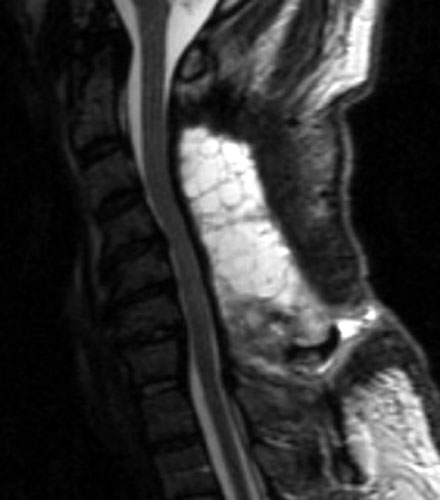

Seroma and Epidural Scar